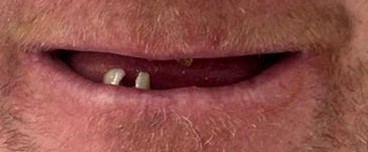

Before

The patient came to our practice because he was frustrated with the remaining broken teeth and wanted a fresh start. He wanted to be able to eat comfortably, improve his appearance, and finally smile with confidence again.

For him, this was not only about teeth — it was also about quality of life, confidence, and comfort.